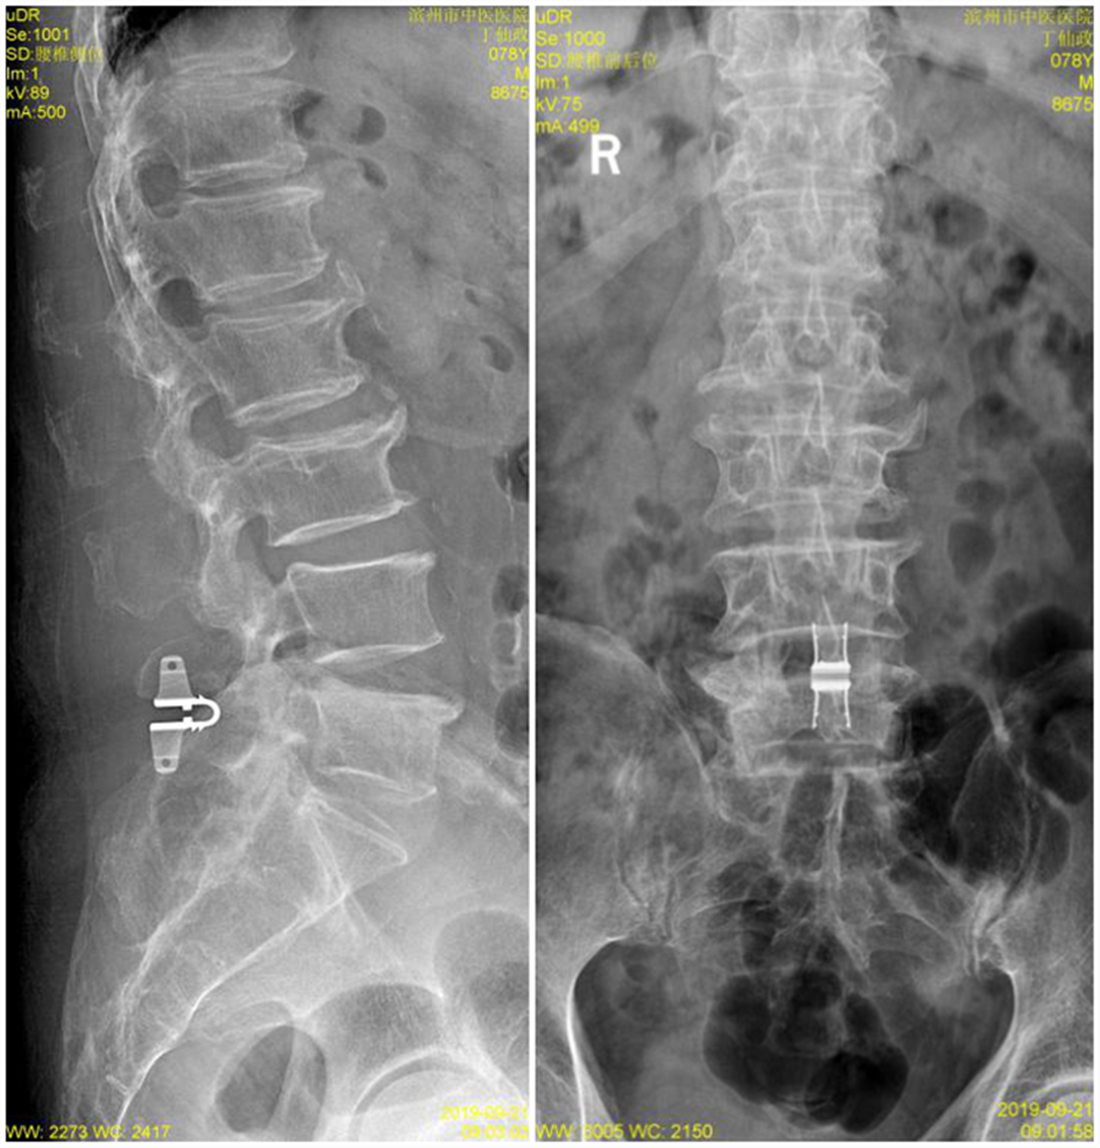

入院后经过详尽询问病史、仔细查体及全面影像检查及分析。患者存在腰部脊椎的纵向的失稳,在站立时存在椎间隙变窄,椎间盘组织进一步突出明显。针对此病患的传统理念,是行腰椎椎弓根螺钉固定加以椎间隙植骨融合术治疗,但由于该患者年龄较大,若以传统理念进行手术,对此高龄患者的创伤较大,恢复期较长。综合考虑后,决定为该患者采取椎板开窗髓核摘除术加以棘突间动态固定(COFLEX)术。

患者术后症状消失,卧床休养5天后佩戴腰围下床活动,腰骶部及右下肢疼痛消失,患者行走情况良好。经影像学检查见椎间盘突出组织摘除完全,硬膜囊及脊神经根减压充分,同时棘突间动态固定系统(COFLEX)位置良好,同时椎间隙高度良好。

术后X线片(L4/5棘突间隙固定物即为COFLEX)